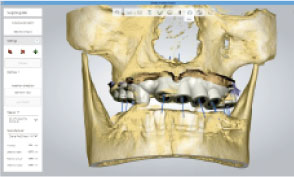

Through virtual operation procedure though 3D computer, DIO NAVI system decreases danger of implant surgery by checking patient's bone tissue and nerve position for planning the optimal surgery procedure and making customized surgical guide.

Not only the mock implant surgery plan that considered the occlusion and stress dispersion, but 3D simulation that can be used as a counseling material for the patient is provided. The doctor can establish a satisfactory treatment plan and with a provided surgical guide, He can operate a safe and accurate procedure.

Through implant planning that considered occlusion and stress dispersion, DIO NAVI Digital Implant System increases the accuracy of the implant treatment and enabled 3D simulation that is used for patient counsel purposes.